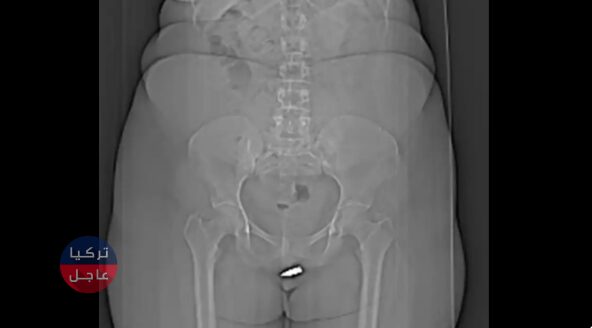

في عملية جراحية فريدة من نوعها، حصلت امرأة من الصومال على رصاصة مأخوذة من بظـ ـر ها. حيث تم إطلاق النار على المرأة التي لم يتم تسميتها بطريق الخطأ من شقة أسفل شقتها بعد أن اخترقت رصاصة السقف بينما كانت جالسة في غرفتها.

وبعد الحادث، تم نقل المرأة على الفور إلى مستشفى أردوغان في مقديشو، وأكد الأطباء أن الرصاصة التي يبلغ طولها 2 سم قد استقرت في بظـ ـر ها.

كما وتم تضمين وقائع قضيتها في تقارير حالة المجلة الدولية للجراحة، وقال المسعفون: “على حد علمنا، هذه هي أول إصابة برصاصة ضالة تخترق منطقة الفرج وتستقر في البـ ـظـ ـر”.

وبعد وضع المرأة تحت تأثير التخدير الموضعي، تمكن الأطباء من استخراج الرصاصة من منطقة البـ ظـ ـر وتمت العملية الجراحية بنجاح وخرجت المرأة من المستشفى في اليوم التالي “بحالة جيدة”. وحتى مواعيد المتابعة بعد شهر أشارت إلى عدم وجود المزيد من الآثار السلبية.